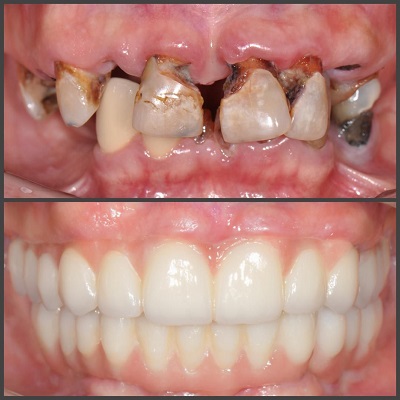

درمانهای ترمیمی: یکی از وظایف اصلی بهترین دکتر دندانپزشک در اهواز، ترمیم دندانهای آسیبدیده است که این شامل پر کردن دندانهای پوسیده، تعویض ترمیمهای قدیمی و ترمیم دندانهای شکسته میشود.

درمانهای زیبایی: یکی از وظایف دندانپزشکان بهبود ظاهر دندانها و لبخند بیماران است که شامل بلیچینگ دندان، استفاده از ونیرهای دندانی و ترمیمهای زیبایی میباشد.

- لمینت سرامیک

- ونیر کامپوزیت

- سفیدکردن دندان ها

- بازسازی تاج دندان

- روکش و بریج